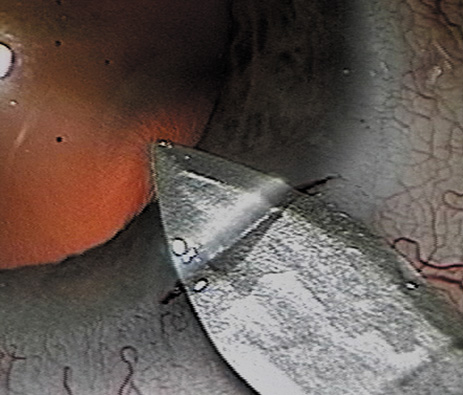

Retrobulbar blocks were among the earliest of orbital block techniques and have stood the test of time. Although there are many approaches to block administration, each technique intends delivery of the anesthetic medication into the intraconal space. These blocks are highly effective (about 95%) in achieving adequate ocular akinesia and anesthesia. Potential complications include retrobulbar hemorrhage,67 globe penetration,68,69 optic nerve sheath hemorrhage, extraocular muscle toxicity with persistent diplopia, and, rarely, brainstem anesthesia. Visualization of the globe is improved when using a transconjunctival approach (Fig. 6) or when the skin is indented with a cotton-tipped applicator (Fig. 7), making globe perforation less likely.

Fig. 6. Retrobulbar block using a transconjunctival approach.